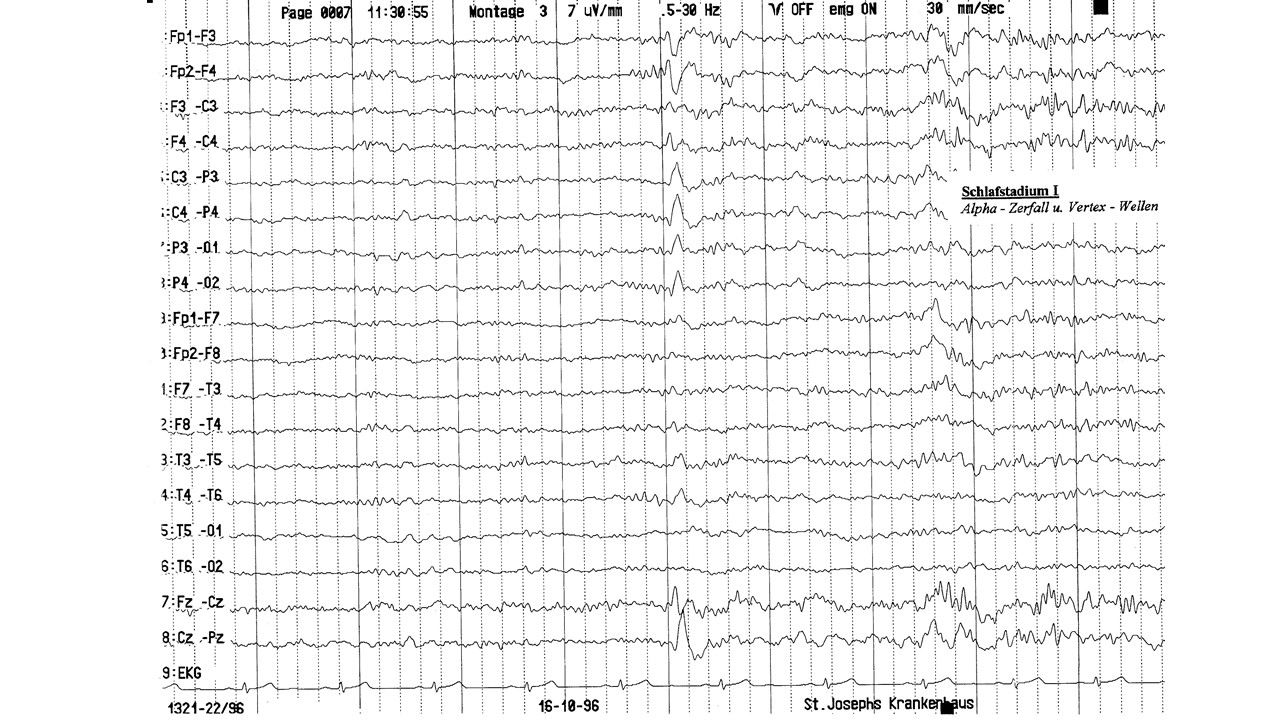

folie82.jpg